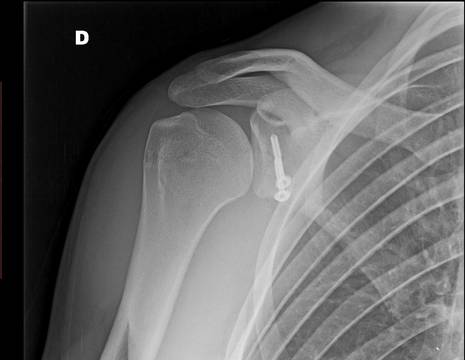

Gli esami richiesti mostrano infatti una grossa lesione ossea sull’omero. Stephan viene pertanto sottoposto ad un intervento di stabilizzazione secondo Latarjet, nonostante la sua giovane età.